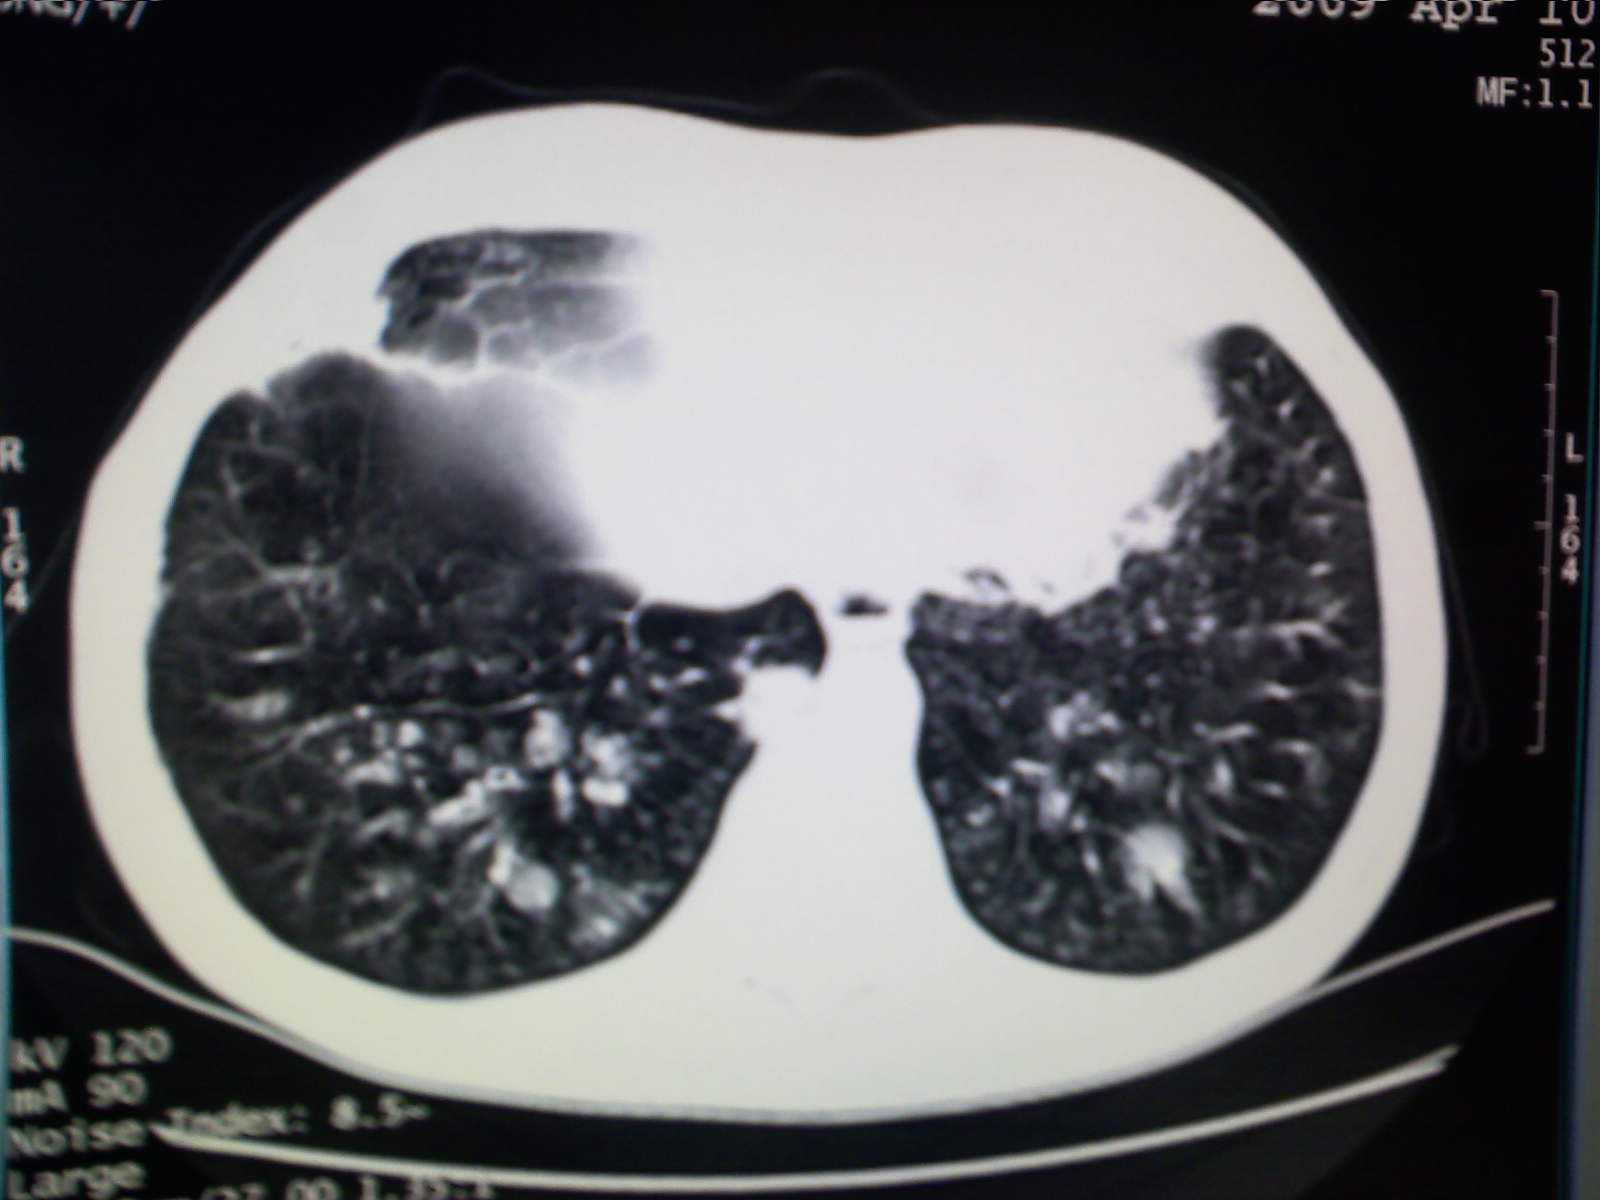

以下是引用卜一在2009-4-11 15:50:00的发言:[br]双肺继发性肺结核伴空洞形成,不排除合并霉菌感染!(病灶呈多形态 多特征 散在分布)。另:合并支气管扩张征伴感染!

以下是引用主力军在2009-4-11 15:55:00的发言:[br]两肺继发性肺结核可能性大。

以下是引用康鹏在2009-4-11 16:30:00的发言:[br]双肺继发性肺结核伴空洞形成合并感染[br]支气管扩张合并感染